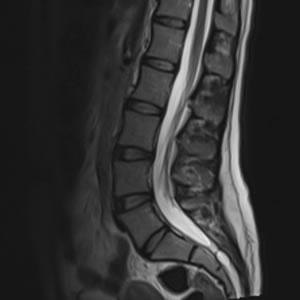

- Investigations – diagnostic scans (MRI, X-ray, CT) arranged promptly, if needed.